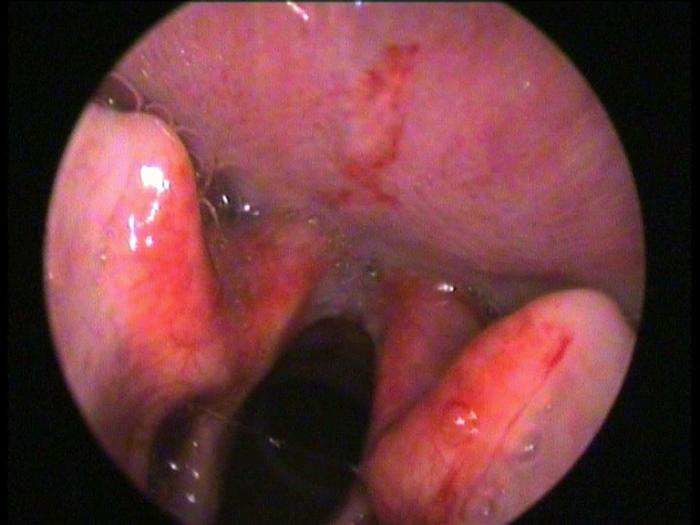

Il termometro che scende drasticamente ed ecco che i più piccoli rischiano di tossire senza sosta “con un suono somigliante a quello della foca o di un cane che abbaia“. E’ colpa della laringite “una patologia respiratoria prevalente in inverno secondaria ad infezioni virali, maggiormente virus parainfluenzali e virus respiratorio sinciziale. Colpisce il 2-3% dei bambini ed è frequente causa di accesso in pronto soccorso. Prevale tra i 6 mesi e i 3 anni di vita, con un picco nel secondo anno“. Lo rilevano gli esperti dell’ospedale pediatrico Bambino Gesù di Roma. “Dopo 2-3 giorni di incubazione, l’esordio della laringite è improvviso, raramente più graduale – sottolineano gli specialisti – La sintomatologia è causata da un rigonfiamento (edema) della mucosa del laringe e delle corde vocali con significativa riduzione dello spazio aereo”. “La tosse è tipicamente somigliante al verso della foca o di un cane che abbaia. Si associano raucedine, pianto afono, stridore, rientramenti inspiratori, irrequietezza. La febbre è di solito non alta – ricordano i pediatri – Nelle forme più gravi, per cattiva ossigenazione, compare una colorazione bluastra (cianosi) intorno alla bocca e alle estremità degli arti, con conseguente senso di forte stanchezza”.

“La laringite è la causa più frequente di stridore laringeo, che deve essere differenziato da altre patologie: reflusso gastroesofageo, laringomalacia congenita, malformazioni vascolari congenite, anelli vascolari, corpo estraneo, epiglottite, laringotracheite batterica, ascesso peritonsillare, allergie“, evidenziano i pediatri che suggeriscono di “tranquillizzare il bambino e prediligere la posizione seduta per ottimizzare la ventilazione. Eseguire una visita medica in caso di primo episodio o solo parziale risposta alla terapia o se si associa difficoltà respiratoria“.